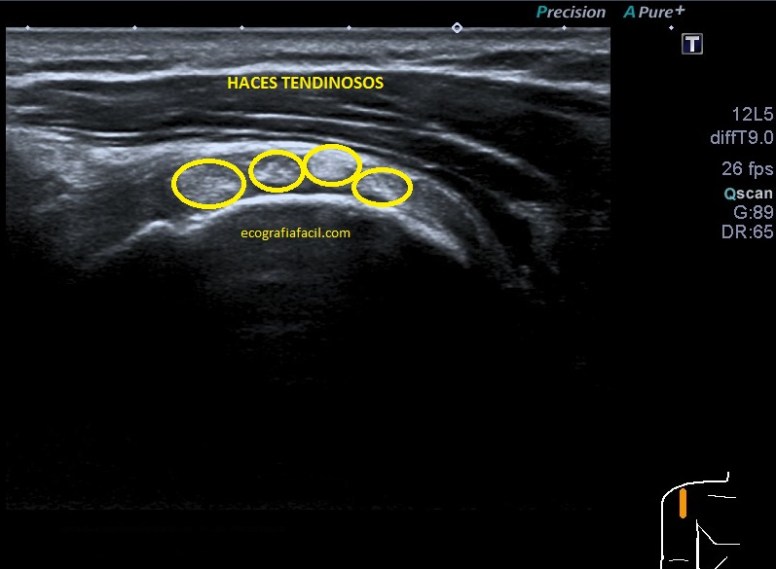

Vamos a partir de la normalidad y te vienes a ver ahora la patología que hoy nos ocupa, mira. En ocasiones podemos encontrarnos la imagen patológica que indica luxación del tendón, imagen 2. Es un corte en Eje corto. Ves la corredera bicipital vacía, el tendón fuera de su localización habitual, hacia medial, como es habitual, pero conservando la ecoestructura.

La imagen número 3 corresponde al corte en eje largo, mucho cuidado, siempre que tengamos el tendón del bíceps luxado, este se irá hacia medial, por eso, en eje largo vamos a encontrar la ecoestructura ligeramente hacia la axila, hacia medial.

Efectivamente, verás que bordeando el tendón existe una mínima cantidad de líquido que está envolviendo u ocupando la vaina del tendón, se ve anecoico y efectivamente es cierto, si lo has visto, enhorabuena, a parte de la luxación, esa es la otra semiología evidente que podemos ver en la imagen 2.